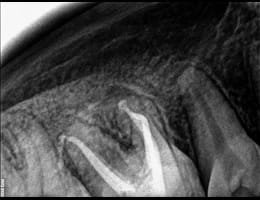

The cleaned canals are filled with a biocompatible material, usually gutta-percha, to seal them and prevent future infection.

gutta core

Superior Filling Materials

GuttaCore: For the best sealing of the root canal system, we use GuttaCore, which provides a 3D fill and superior adaptation to the canal walls.

Lateral Condensation: This technique allows for a dense and well-sealed root canal filling, preventing reinfection and promoting long-term success.